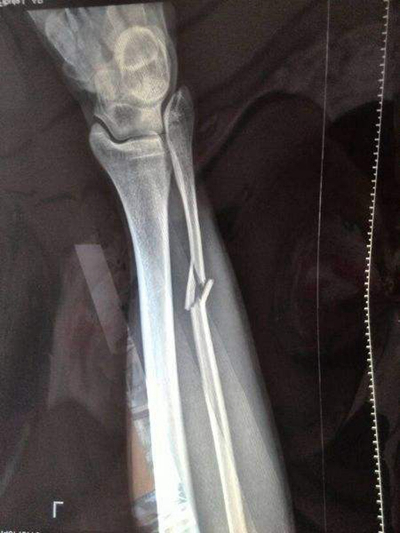

骨折圖片